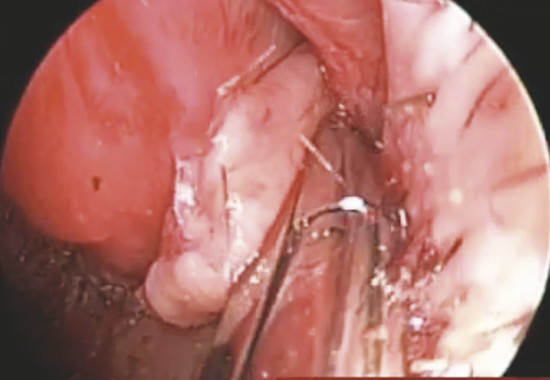

The mucoperiosteal graft is then inserted through the hemitransfix incision in the tunnel between the septal cartilage and elevated septal mucoperichondrial flap (Fig. 19‑8).

Graft borders are positioned under the previously elevated perforation borders in underlay fashion for minimum 5 mm all around (Fig. 19‑9).

At the end of this step, no one area of the perforation has to be uncovered (Fig. 19‑10).